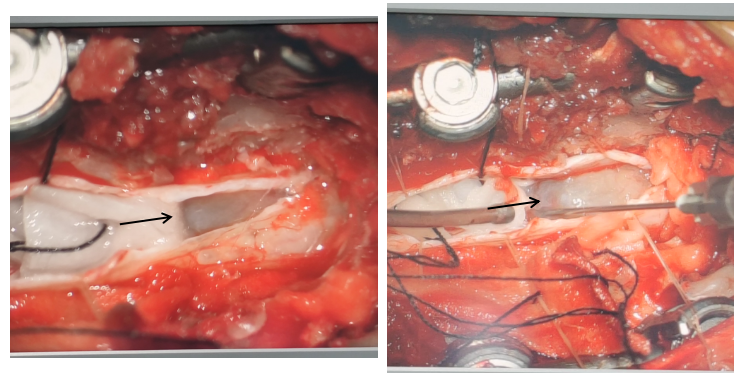

箭头表示手术中显微镜下的肿瘤

箭头表示手术切除下来的肿瘤

说起来,咱今天为啥要说椎管内肿瘤呢?那还得从一位冯奶奶说起。这个冯奶奶今年79岁了,平时嘛身体还行,除了高血压之外倒也没得过什么病。但是20年12月左右,她开始感觉肩背不舒服,就是肩背隐隐的痛,特别到了晚上疼得厉害。刚开始嘛,觉得没啥事,脖子疼么,上年纪了,谁还没个头疼脑热的。可是慢慢的这冯奶奶觉着老这么疼着也不是个事儿,就在21年1月份找了家医院做了个核磁共振检查。这一查可不得了,胸椎管里长了个东西,看起来吧像是个肿瘤,医院的医生们就建议要做个手术,切掉!家里人一合计,让瘤子一直长在那儿也不是个事儿,该切嘛还是要切,就到咱们医院来了。去了神经外科住院,做完检查明确了胸椎管里的东西就是肿瘤之后请了咱们脊柱外科会诊,两个科室一起定了手术方案,然后过了两天两个科室联手做了一台手术把瘤子给取了出来。

最后再说一说治疗,椎管内肿瘤还是以手术治疗为主,患者身体情况差不能耐受手术者才采用放射治疗。所以啊,大家要是真的发现了这个问题可得早点来找咱们彭医生哟~